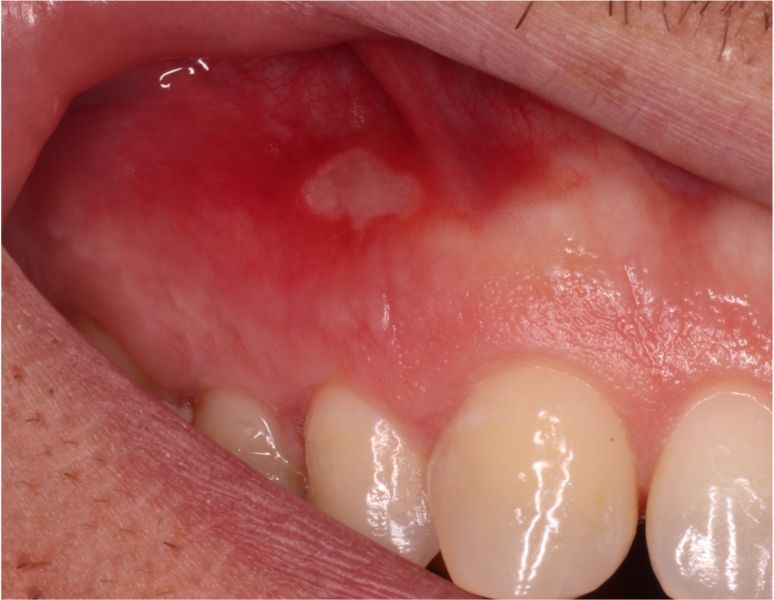

Un afta es una pequeña úlcera o llaga redondeada, dolorosa, de color blanquecino o amarillo con un borde rojizo que aparece en la boca de forma inesperada.

Frecuentemente, se suelen localizar en lengua, encías, paladar, labios o por dentro de las mejillas. Suelen curarse por sí mismas en unos días, pero durante ese tiempo el paciente siente dolor e incluso puede dificultarse la alimentación o el habla.